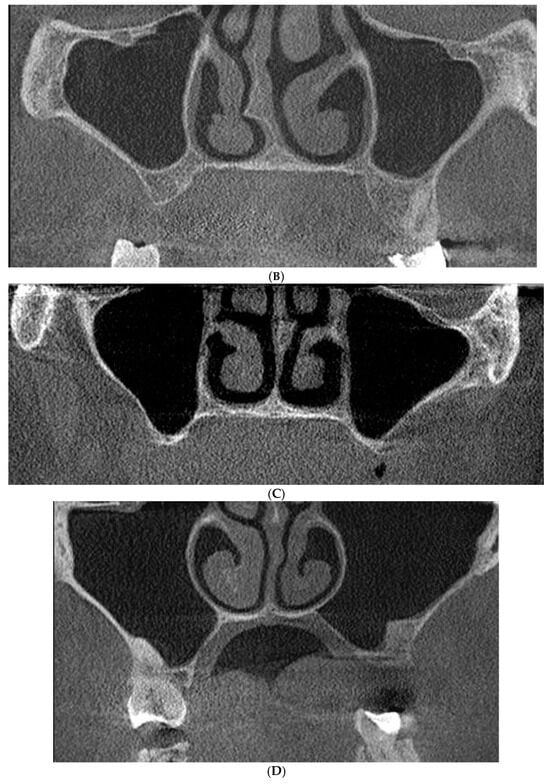

Class 0: There is an adequate sub-sinus residual bone height, which is not indicated for direct maxillary sinus elevation (Figure 2A). The incidence of this finding was 4%.

Figure 2.

Evaluation of the maxillary sinus based on cone beam computed tomography (CBCT) scans in the coronal view. (A) Class 0: Adequate sub-sinus alveolar bone height. (B) Class 1: Reduced sub-sinus alveolar bone height with a thin lateral wall. (C) Class 2: Reduced sub-sinus alveolar bone height with comparable thickness of the lateral and palatal walls. (D) Class 3: Reduced sub-sinus alveolar bone height with a thin palatal wall.

Class 1: There is a reduced sub-sinus residual bone height with a thinner lateral sinus wall in comparison to the palatal wall (Figure 2B), which can be indicated for the lateral window osteotomy technique because buccal access is presumably easier. The crestal window osteotomy technique can also be applied. The incidence of such variant was common (44%).

Class 2: There is a reduced sub-sinus residual bone height with the lateral and palatal sinus walls having a comparable thickness (Figure 2C), which can be indicated for either lateral or palatal window osteotomy. The crestal window osteotomy technique can be utilized as well. This variant was evident in almost half of the obtained scans (49%).

Class 3: There is a reduced sub-sinus residual bone height with a thinner palatal sinus wall in comparison to the lateral wall (Figure 1 and Figure 2D), which can be indicated for the palatal window osteotomy technique or crestal window osteotomy technique. This was the most uncommon variant (3%), which might be logical as the palatal bone is usually denser and thicker [21].

The most common variant was the comparable thickness of the lateral and palatal sinus walls (Figure 2C), in which either the lateral, palatal, or crestal window osteotomies can be applied (49%).